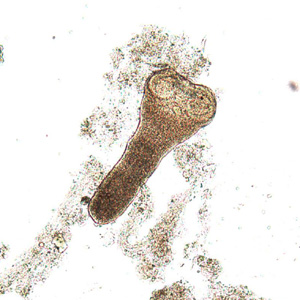

Fasciolosis buski

Fasciola hepatica